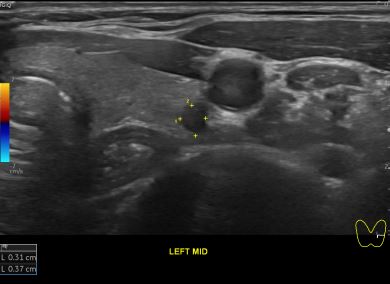

상기환자 외부건진 갑상선 이상소견으로 조직검사위해 내원하신 30대 중반 여성분으로

의심스러운 갑상선 좌엽 세포검사후 갑상선암으로 진단되었습니다